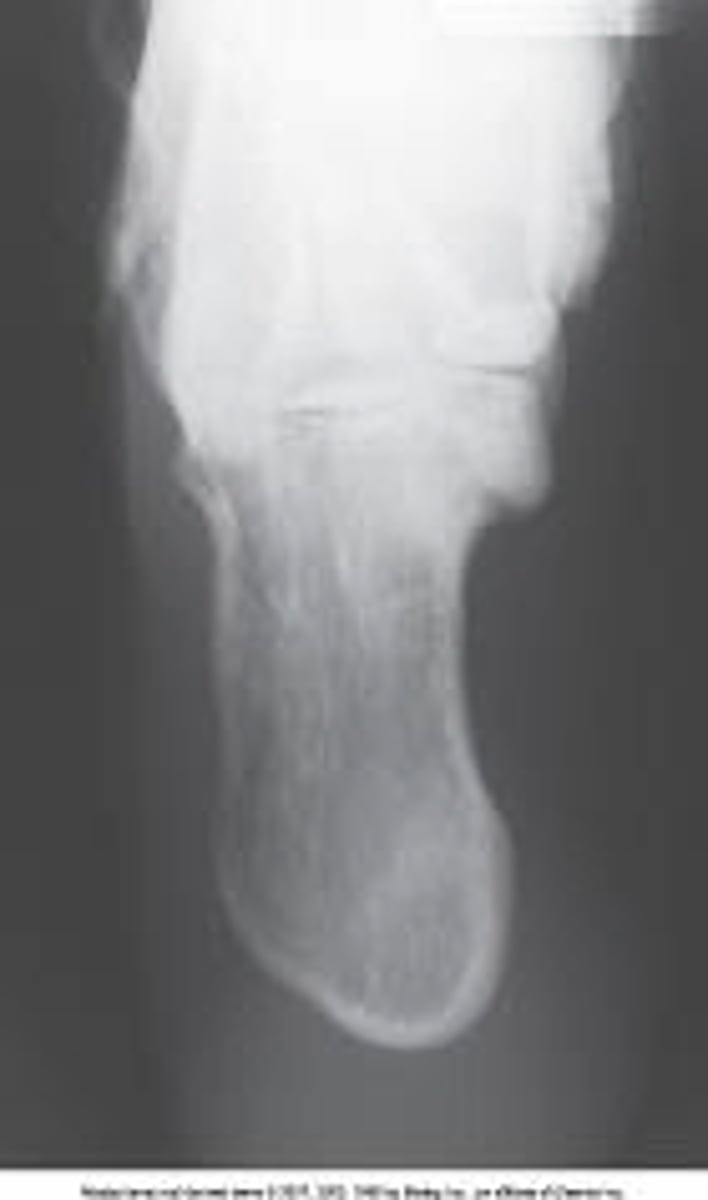

Plantodorsal axial calcaneus

What is the projection and anatomy of interest in the image below?

AP axial calcaneus

AP calcaneus

Superoinferior axial calcaneus